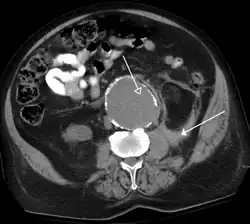

The most common technique is to perform portal venous phase imaging in the abdomen and pelvis (approximately 60–90 seconds after contrast administration, figure 2). This results in near optimal contrast opacification of the majority of the solid abdominal organs and it is used for a wide variety of indications: nonspecific abdominal pain; hernia; infection; masses (with a few exceptions such as hypervascular, renal, and some hepatic tumors); and in most follow-up examinations. As a general rule, this single phase is adequate unless there is a specific clinical indication that has been shown to benefit from other phases.

![FIGURE 2. Contrast enhanced CT demonstrating parenchymal enhancement of the intra-abdominal organs in the portal venous phase (axial left, coronal reformat right).[citation needed]](./_assets_/Normal_contrast_enhanced_abdominal_CT.jpg) FIGURE 2. Contrast enhanced CT demonstrating parenchymal enhancement of the intra-abdominal organs in the portal venous phase (axial left, coronal reformat right).

FIGURE 2. Contrast enhanced CT demonstrating parenchymal enhancement of the intra-abdominal organs in the portal venous phase (axial left, coronal reformat right).